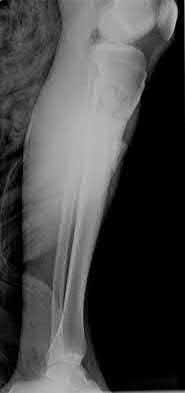

3. # Which of the following is not an appropriate implant for treatment of the fracture seen in Figure A?

The image shows a reverse obliquity intertrochanteric hip fracture.

According to the referenced article by Haidukewych et al, unstable peritrochanteric hip fractures have a worse outcome (failed in 9/16 cases) if treated with a sliding hip screw. Two additional factors that were found to have a strong correlation with postoperative failure (nonunion, loss of reduction) were poor reduction and poor implant placement. In this study, fixed angle devices were superior. Intramedullary fixation has the added advantage of a shorter lever arm and less potential for fracture collapse and limb shortening.

The IMN also acts as a medial buttress.

According to Sanders et al, the dynamic condylar screw (DCS) can also be used in subtrochanteric models, but should not be used if extensive comminution is seen, as they reported a high failure rate with DCS in these fractures if highly comminuted. They report a 77% overall union rate with this device.